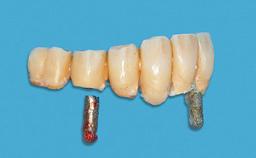

The patient presented with root fracture of the right central incisor with associated distal bone loss. After sectioning and extraction of the fractured root the distal papilla was lost, creating an esthetic compromise. This case demonstrates an option for treating this esthetic compromise. Early (Type 2) implant placement was performed at 7 weeks with simultaneous horizontal and vertical augmentation using Bio-Oss and Bio-Gide (Geistlich). After 3 months a connective tissue graft was performed at the time of implant exposure. Despite these surgical procedures, the papilla could not be recovered. As a result, a prosthetic solution was necessary.